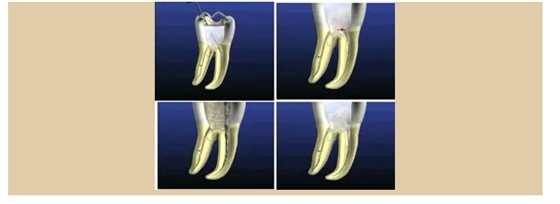

二、根管預(yù)備后形態(tài)

牙體缺損的修復(fù)需要將剩余牙體組織制備成一定形態(tài),以利修復(fù)體的良好固位。根管充填為了致密封閉根管系統(tǒng)也需要良好的根管預(yù)備后形態(tài)。

常規(guī)概念的根管預(yù)備后形態(tài)有: ( 1 )便宜形態(tài)( convenience form )。 ( 2 )保持形態(tài)( retention form )。

常規(guī)概念的根管預(yù)備后形態(tài)有:

( 1 )便宜形態(tài)( convenience form )。 ( 2 )保持形態(tài)( retention form )

( 3 )抵抗形態(tài)( resistance form )。

1. 便宜形態(tài)

便宜形態(tài)是自切端或咬頜面朝向根尖的直線開擴(kuò)尖錐形態(tài),減少污染物推出根尖孔,方便沖洗、根管充填和側(cè)壁施壓。

2. 保持形態(tài)

保持形態(tài)是根尖狹窄部?jī)?nèi) 1 — 2mm 的一段距離,由擴(kuò)大器回轉(zhuǎn)切割而不貼根管壁提拉切割制成,是擴(kuò)大器的原始形態(tài)(近似平行)。在測(cè)試主牙膠尖時(shí)給測(cè)試者有一個(gè)牽引抵抗 (tugback) 的感覺。

3. 抵抗形態(tài)

抵抗形態(tài)是根管預(yù)備的根尖形態(tài),它是由擴(kuò)大器或根管銼尖端 75 度角自然切割而成。其目的是防止根管充填材超出根尖孔,并且使根尖封閉更加嚴(yán)密。